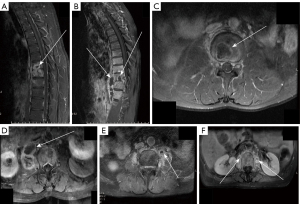

In fluid-sensitive sequences, involvement of posterior elements did not differ among the four groups. However, several other parameters were significantly different across the groups: vertebral body signal on T2WI (Infected vertebrae/normal vertebrae on T2WI), extent of vertebral destruction, presence of skip lesions, and endplate inflammatory reaction line (Figure 2). The degree of disc destruction also varied among the groups. The FS group exhibited significantly lower vertebral body signal intensity on T2WI images compared to the other groups (Figure 2). The incidence of severe vertebral body destruction was notably lower in the BS group compared to the TS and FS groups. The BS group was also more likely to have skip lesions than the PS group, although the incidence of skip lesions did not differ significantly between the TS and BS groups (Figure 3). Additionally, the FS group had a much higher incidence of endplate inflammatory reaction line compared to the other groups, while the PS group showed a higher incidence of this feature than the TS and BS groups (Table 4).

In T1-weighted contrast-enhanced sequences, the occurrence of paravertebral abscesses did not differ significantly across the four groups (Table 5). However, when paravertebral abscesses were present, there was a significant difference among the groups. Epidural abscesses did not show significant differences across the groups. Vertebral intraosseous abscesses, on the other hand, exhibited significant differences among the four groups. In cases where paravertebral abscesses were present, the likelihood of having a large paravertebral abscess was significantly higher in the TS group compared to the other groups (Figure 4). Additionally, vertebral intraosseous abscesses were more prevalent in the TS group than in the other groups (Figure 4).

In the study by Gupta et al., thoracic spine involvement, posterior element involvement, and spinal deformity were considered independent predictors for the diagnosis of TS (12). However, Batirel et al. analyzed data from a large sample of TS patients and found that lumbar spine involvement was more prevalent than thoracic spine involvement (45), which challenges the notion that thoracic spine involvement is an independent diagnostic factor for TS. Nonetheless, other studies support the findings of Gupta et al. (6,19,46,47). Multiple vertebral body involvement in the TS group has been frequently reported in prior studies and has become a characteristic feature of TS (6,15,48,49). However, the present study unexpectedly found that the percentage of multivertebral involvement in the BS group was significantly higher than that in the PS group. Additionally, the incidence of jumping lesions in the BS group did not differ from that in the TS group, which is an unusual finding not previously reported. In fact, this prevalence of multivertebral involvement in the BS group exceeds the 5–21% range reported in prior studies on Brucella spondylitis (50,51). Previous pathological studies have shown that BS often spreads through the vertebral venous plexus, a pathway also discussed in the context of jumping lesions in TS (52-54). This may provide a potential mechanism for the occurrence of jumping lesions in BS.